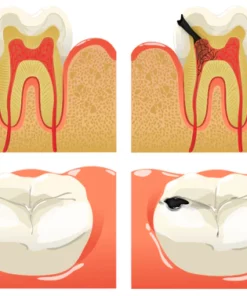

Dental caries develop when germs damage tooth enamel and gradually penetrate into the dentin and even the pulp. This can result in bad breath, toothaches, weakened teeth, and potential tooth loss. The presence of caries often triggers a chain reaction, causing healthy teeth to be affected as germs spread to adjacent teeth.